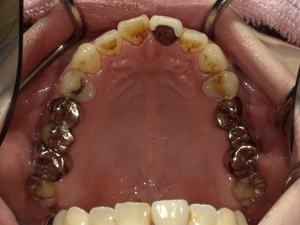

〇ご相談内容:歯並びがよくない〇矯正の種類:マウスピース型矯正「インビザライン」〇治療期間:39週間〇治療費用:44万円(税込)